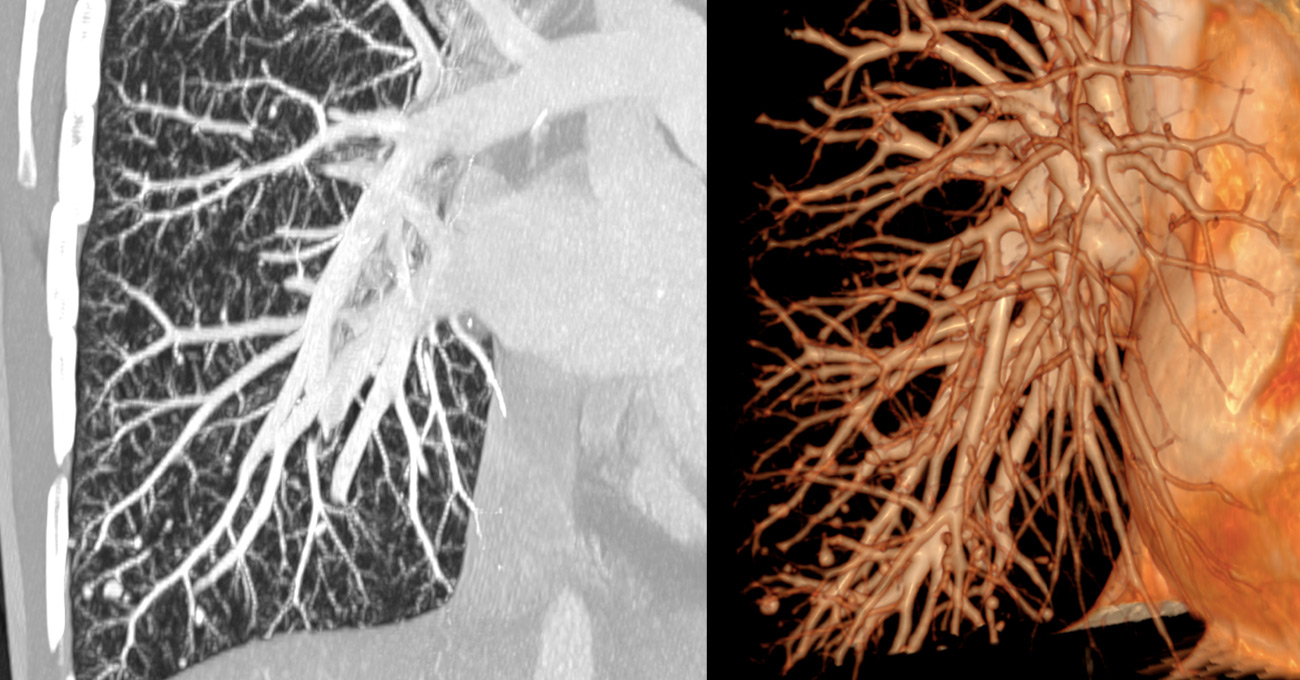

Figure 1

Maximun intensity imaging and 3D reconstructions of pulmonary computed tomography angiography showing numerous pulmonary arteriovenous malformations in a female 50 years old female patient known to have hereditary haemorrhagic telangectasia.